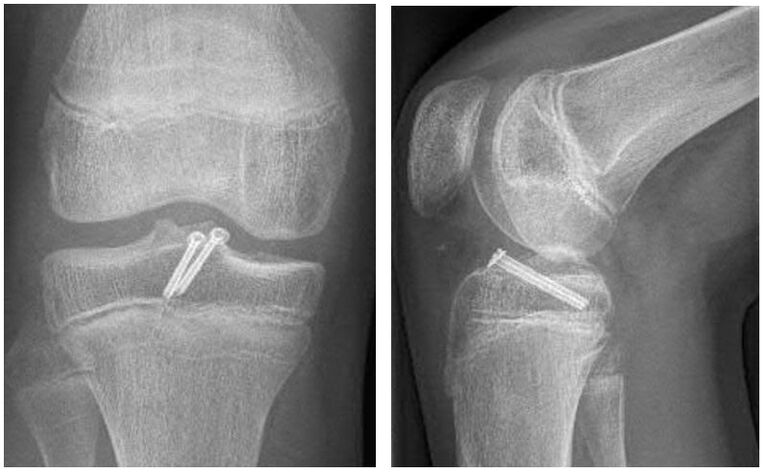

Eine Sonderform der Kreuzbandverletzung ist der knöcherne Ausriss des Bandes. Dabei kommt es bei der Verletzung nicht zu einer Ruptur des Bandes, sonders das Kreuzband reist mit einem Knochenstück ab. Meist ist dieser Ausriss dabei am Schienbeinkopf lokalisiert. Besonders gefährdet sind Kinder und Jugendliche, da bei diesen der Knochen meist weicher als die Bandstruktur ist. Die Symptome und Beschwerden entsprechen einer Kreuzbandruptur. Oft können die Verletzten das Bein nicht richtig strecken, da das Knochenstück einklemmt. Diese Verletzung ist im Gegensatz zu einer Kreuzbandruptur oft auch im normalen Röntgenbild des Kniegelenkes zu sehen. Zur Sicherung der Diagnose und um nach eventuellen Begleitverletzungen zu suchen, erfolgt oft ein MRT und manchmal auch eine Computertomographie (CT).